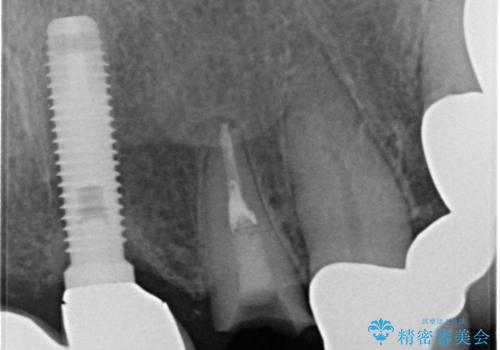

- 以前から頻繁に前歯が土台から外れてしまうことがあり、インプラントによる治療を希望して来院された患者様です。

歯根が割れていることはありませんでしたが、残っている歯質が全て歯肉よりも深い位置にあるため、土台としての機能は不足している状態でした。

歯根周辺の骨や歯肉の状態は良く、抜歯して速やかにインプラントを埋入し、即日で仮歯を装着するプランにて治療を行うこととしました。